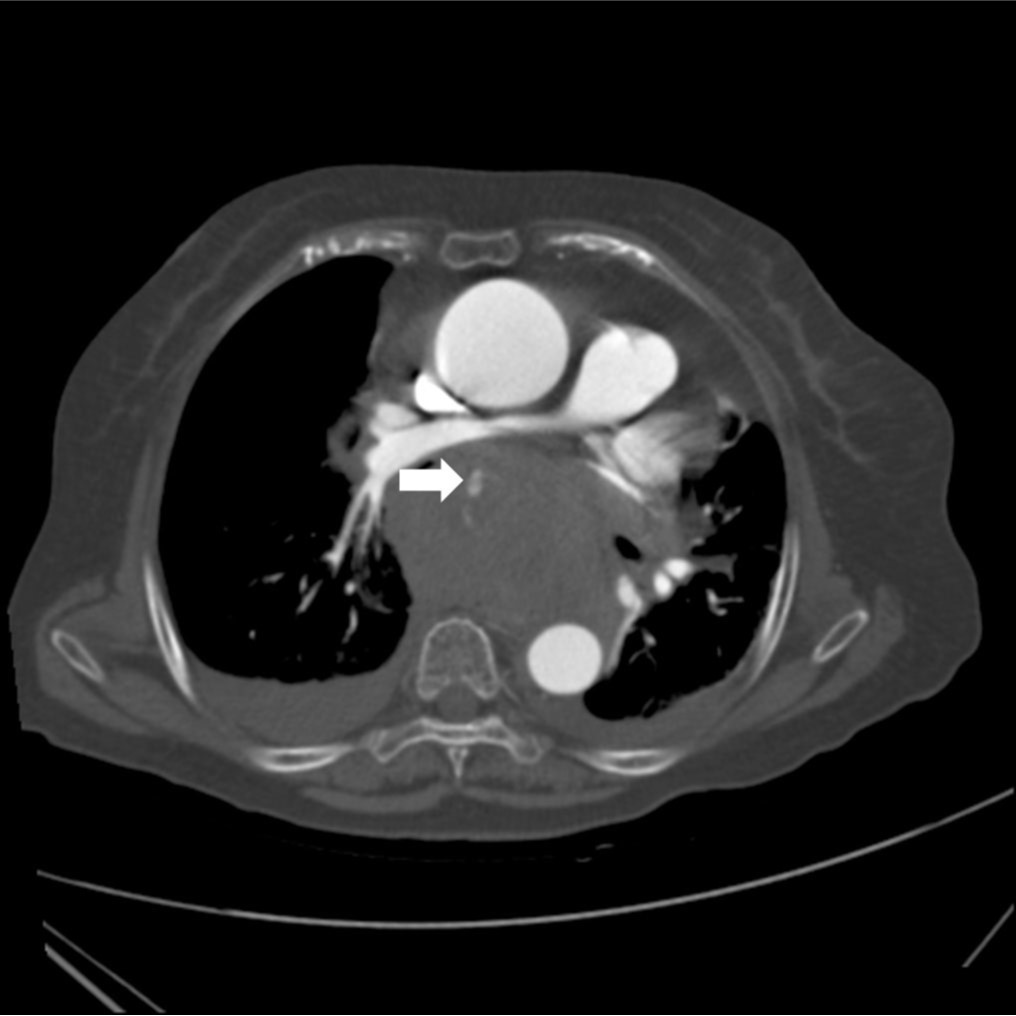

Fig. 2A, B. Axial CT images reveal a large hematoma with extravasation of contrast media (arrow) in the posterior mediastinum. The extravasation was connected with the right bronchial artery (arrowhead) originated from the descending thoracic aorta.